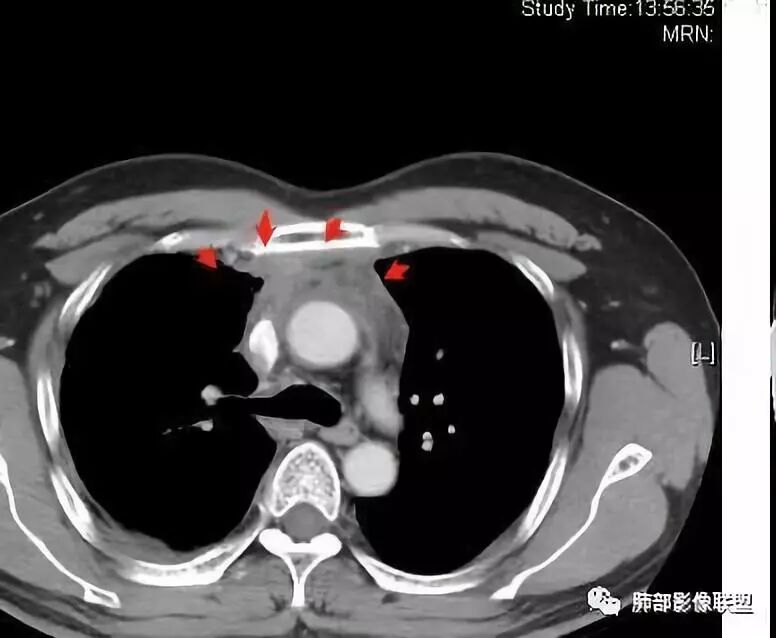

南边:大家看看前纵隔的病灶,符合肿瘤吗脂肪,周围密度增高

三个石头:比较散;像炎症的蔓延生长南边:是,这些看着心里不踏实觉得把这个纳入肿瘤去考虑是否合适总觉得边缘收缩的、散在的朝周围蔓延;中央还跨过脂肪,朝对侧胸膜蔓延把这个与囊性病变连到一起去考虑是否还需要斟酌一下因为这个就方向差异大了南边:连在一起,囊实性,边界不清,自然考虑恶性:如果独立,囊张力高、边界清楚,间隔,自然朝良性考虑:

Coke with ice:囊性部分考虑包裹性积液?南边:不是积液;有间隔;张力高;而且位置有些特殊

大家仔细看看积液中的游离气体;

不是支气管,是积气;是穿刺进去的;

囊内密度不一致

我认为囊张力高,积液中的气体均在周围,外侧、下方,囊内有间隔:各腔密度不一致;提示:囊腔属于前纵隔,不是包裹性积液;现在的问题:囊腔与内侧的病灶是否是一体的

南边:我总觉得这个纵隔内不像是一个肿块的改变,扁平,周围蔓延:有符合炎性的的特点,或者肿瘤的侵犯;但是肿瘤的侵犯,不大符合,实性部位的边缘过于柔和,没有毛糙的侵犯边缘。